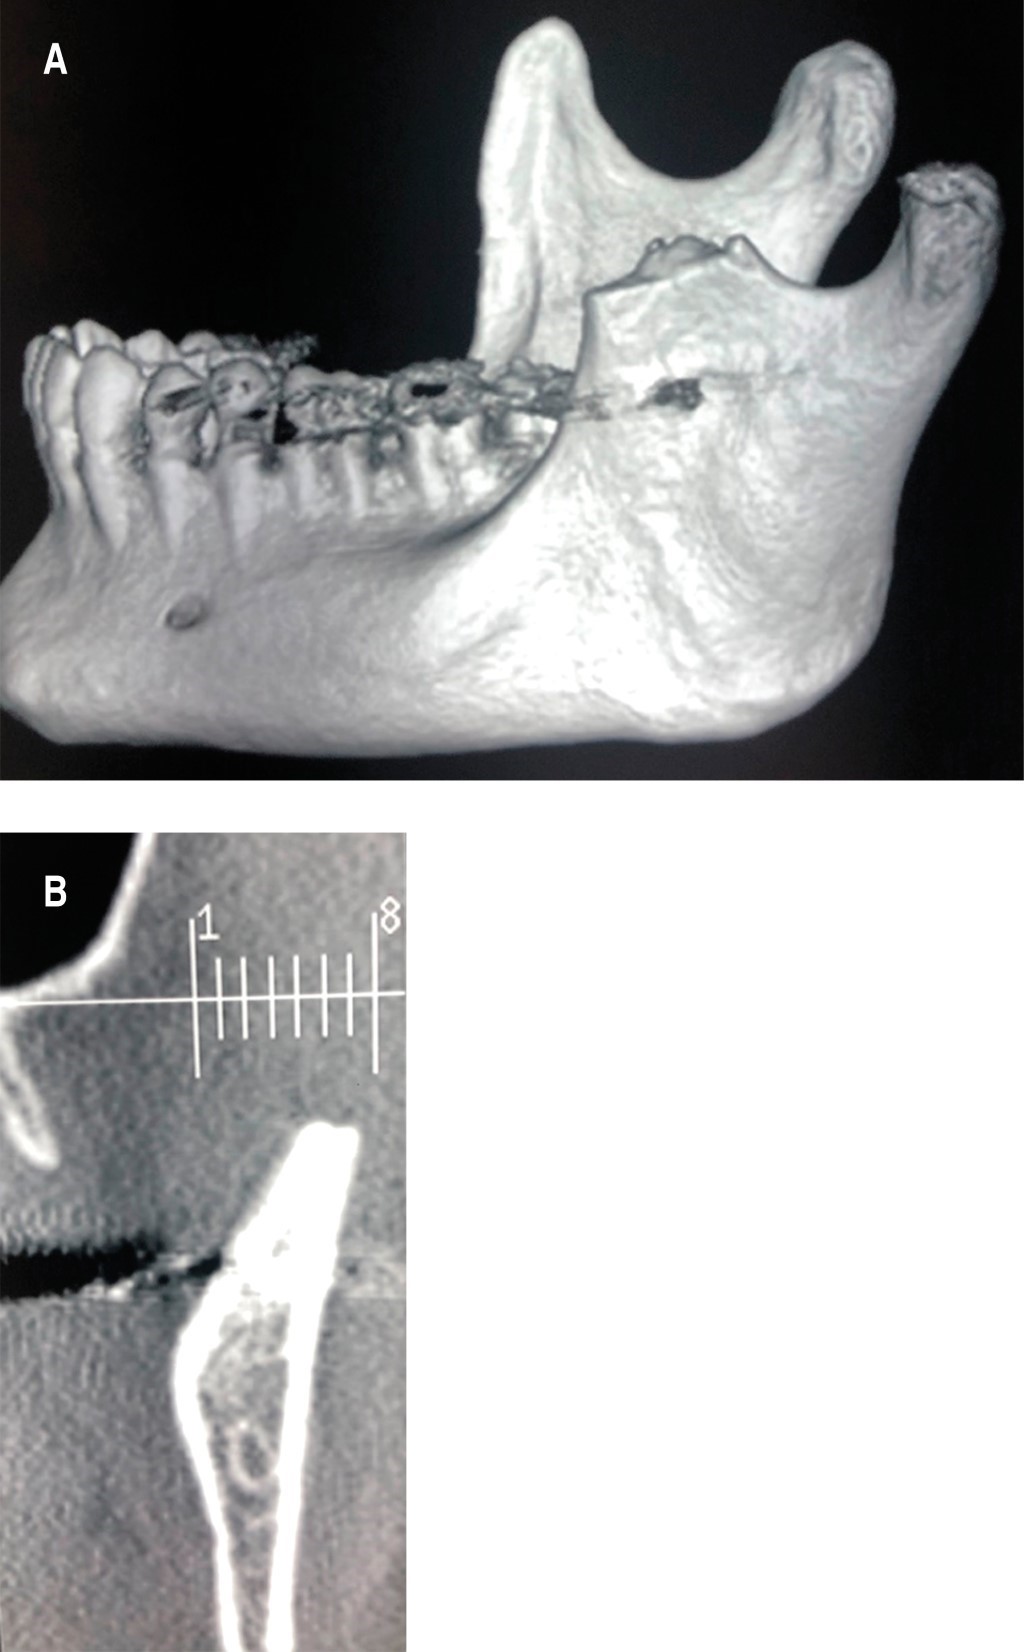

En la RMN se observa una lesión en la apófisis coronoides del lado izquierdo (Figura 4). En la ciudad de Bahía Blanca, Buenos Aires, Argentina donde desarrollamos nuestra práctica, no contamos con tomógrafo computarizado de haz cónico de Fov amplio, por lo tanto, se solicita una tomografía computarizada multislice, en la cual se verifica una lesión tumoral en la apófisis coronoides izquierda con forma de hongo, que se introduce entre el arco cigomático y el maxilar desplazando ambas estructuras (Figuras 5 y 6).

Figura 5

Figura 6